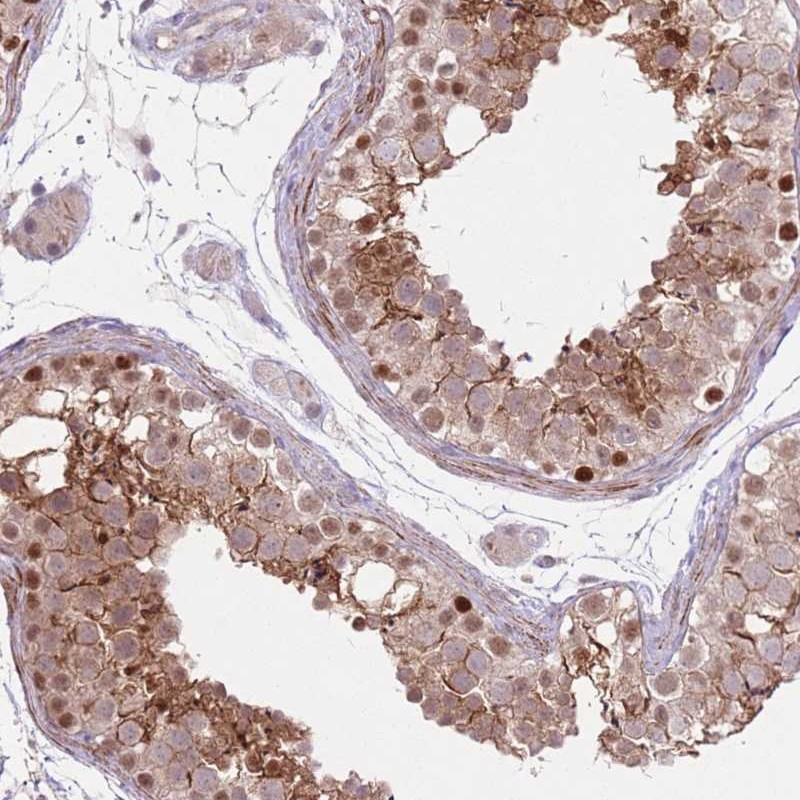

Immunohistochemical staining of human testis shows moderate cytoplasmic and nuclear positivity in cells in seminiferus ducts.